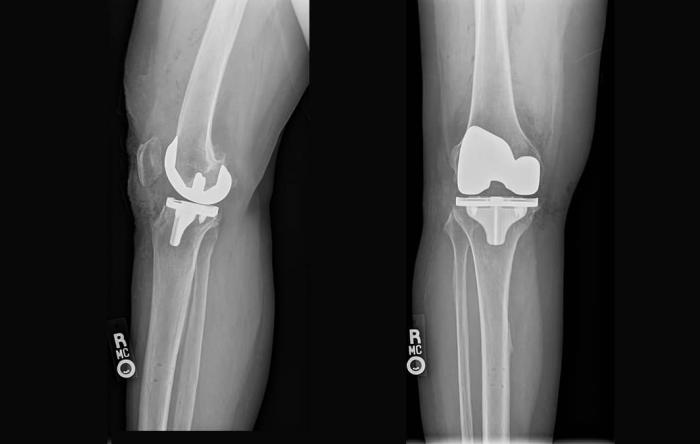

ACL surgery is performed more than 100,000 times...